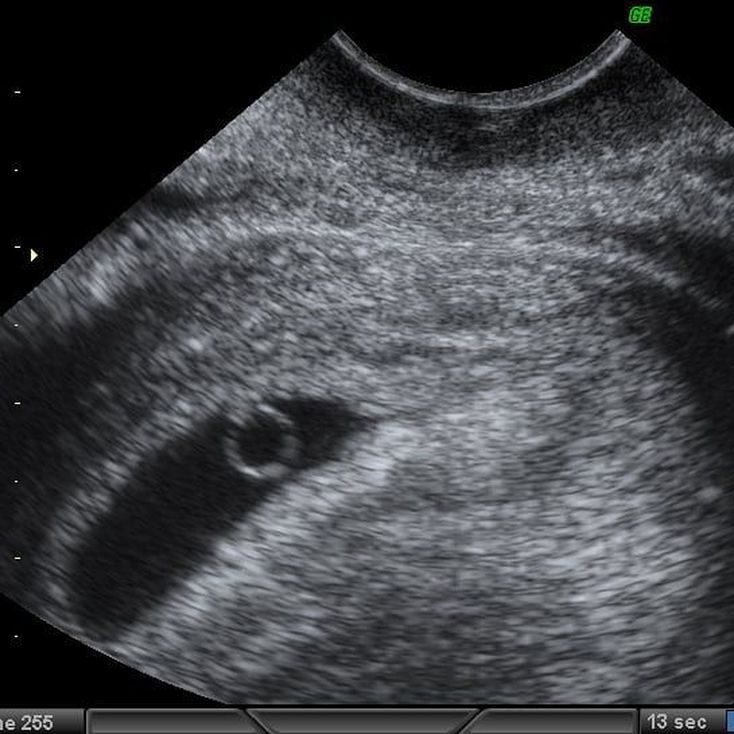

Sonograms at 5–6 weeks of gestational age depict the embryo as a focal thickening at the periphery of the yolk sac—an appearance referred to as “diamond ring” sign. The yolk sac represents the “ring” and the embryo represents the “diamond” in this earliest sign of embryonic development. In case your ultrasound looks like this, congrats!